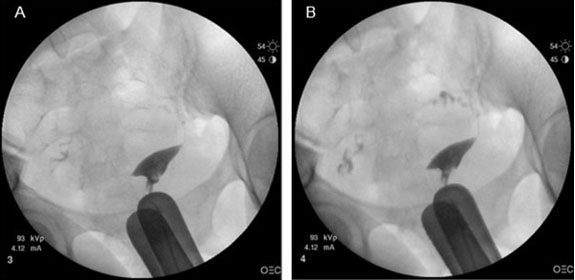

Case Report: We report the case of a 31-year-old female with a history of an umbilical hernia repair who presented with acute abdominal findings at 22 weeks gestation attributed to delayed infection of surgical mesh.